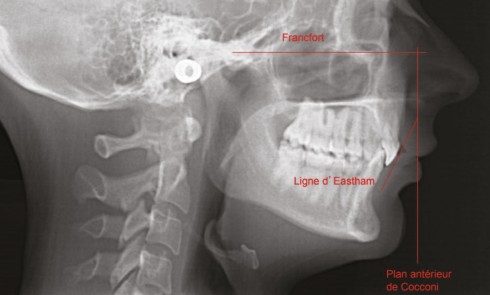

Article réservé à nos abonnés Étude prospective de suivi céphalométrique à dix ans

Le traitement optimal pour les patients atteints de syndrome d’apnées hypopnées obstructives du sommeil (SAHOS) sévère est la pression positive...